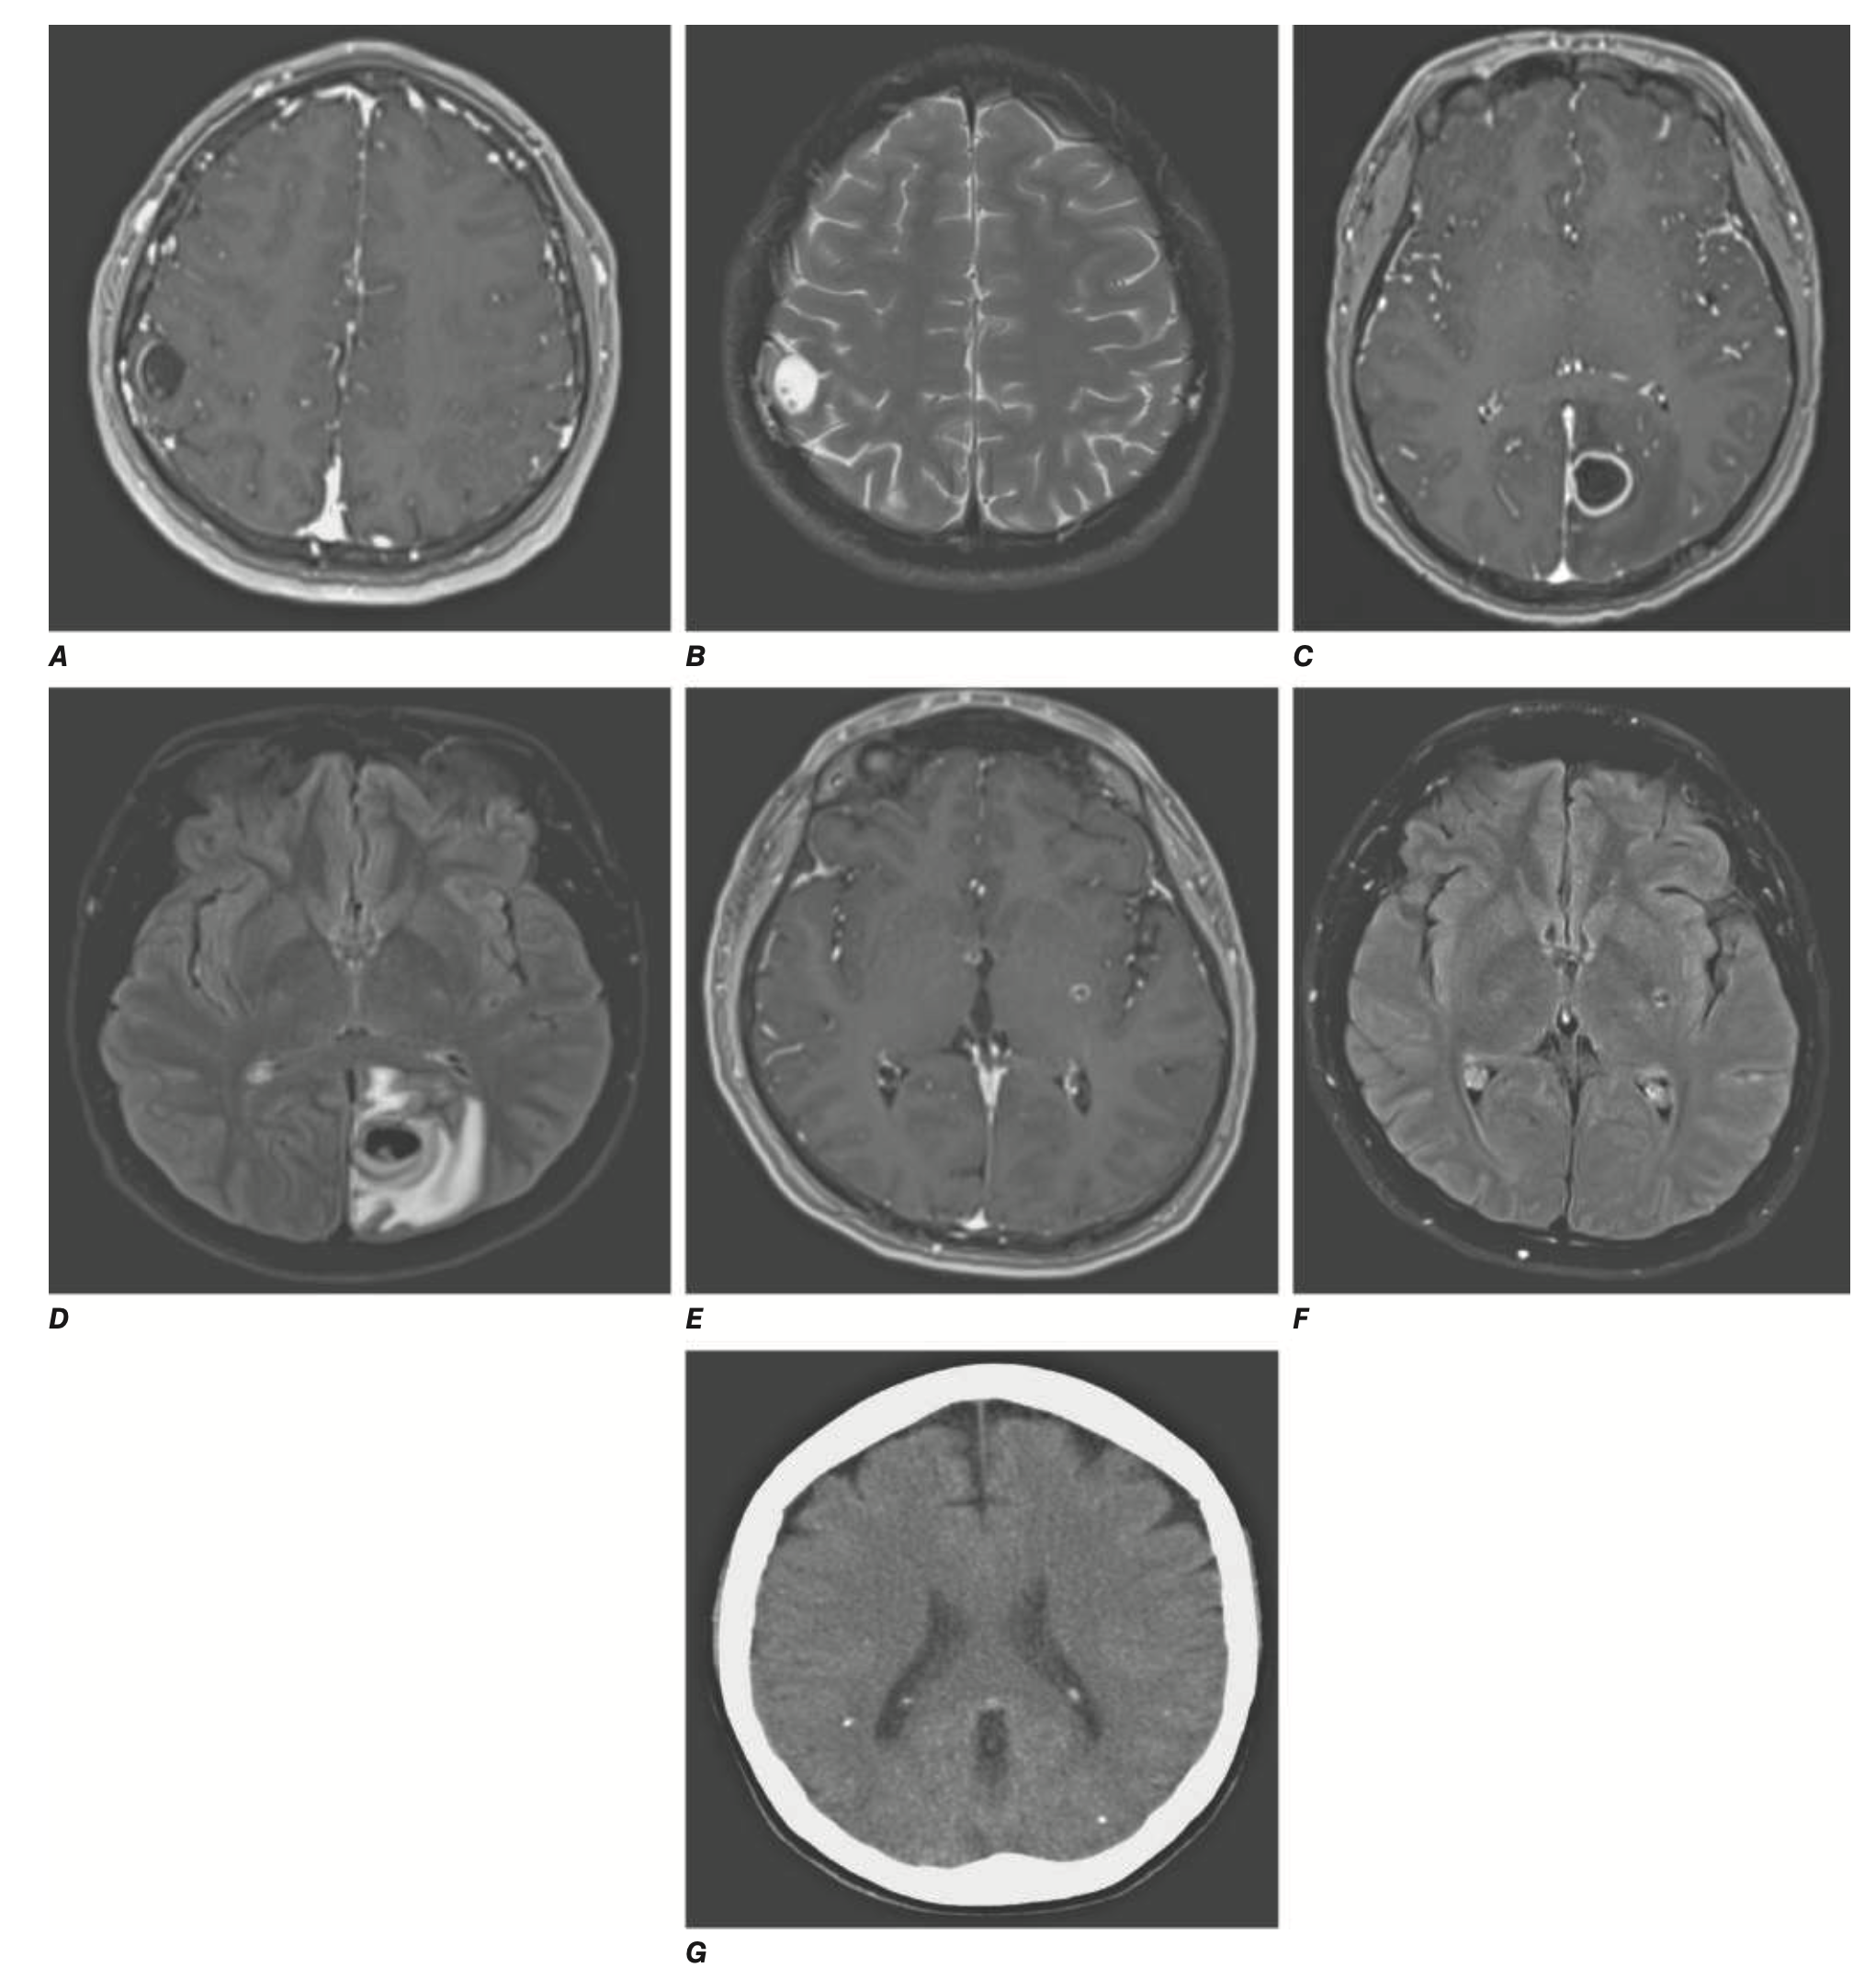

• 조영증강 뇌 영상(CT/MRI with CE): Cyst with scolex (Scolex가 있는 낭종), 다발성 석회화(Calcifications)

A.B: vesicular stage

C.D: colloidal stage

E.F: granulonodular stage

G: nodular calcified stage